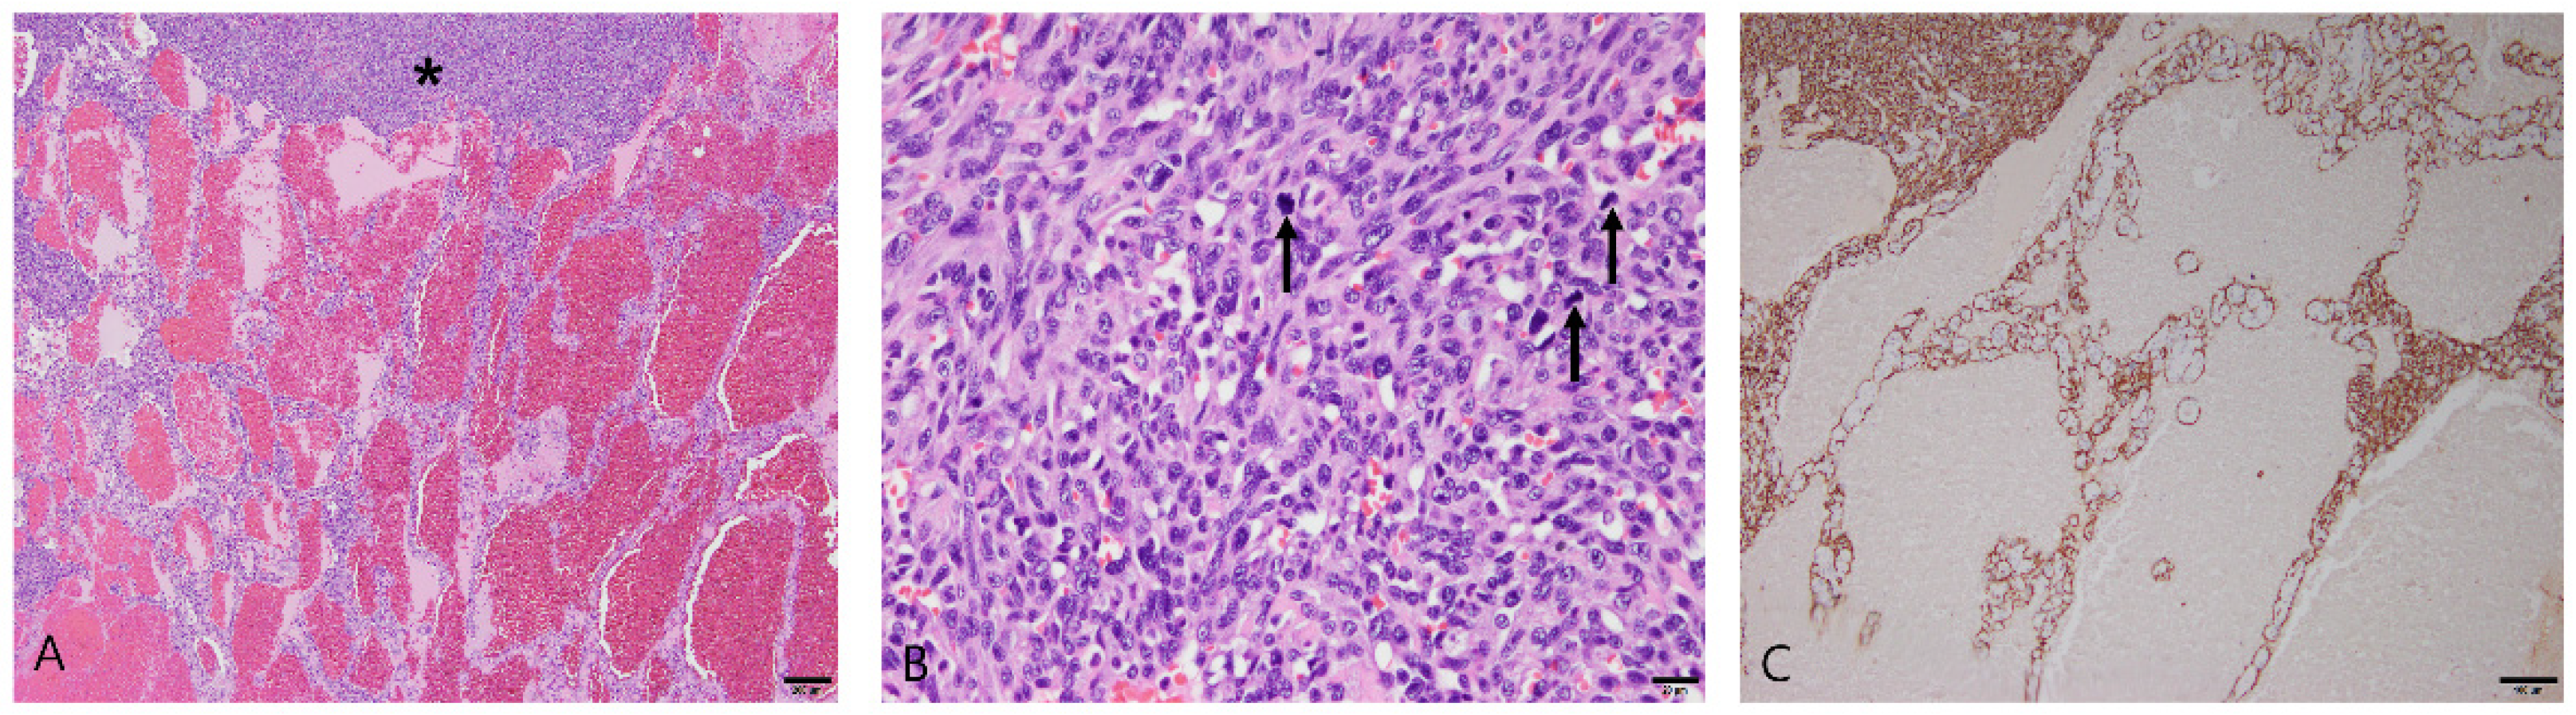

3.2.4. Splenic Lymphoma

3.2.5. Stromal Sarcomas